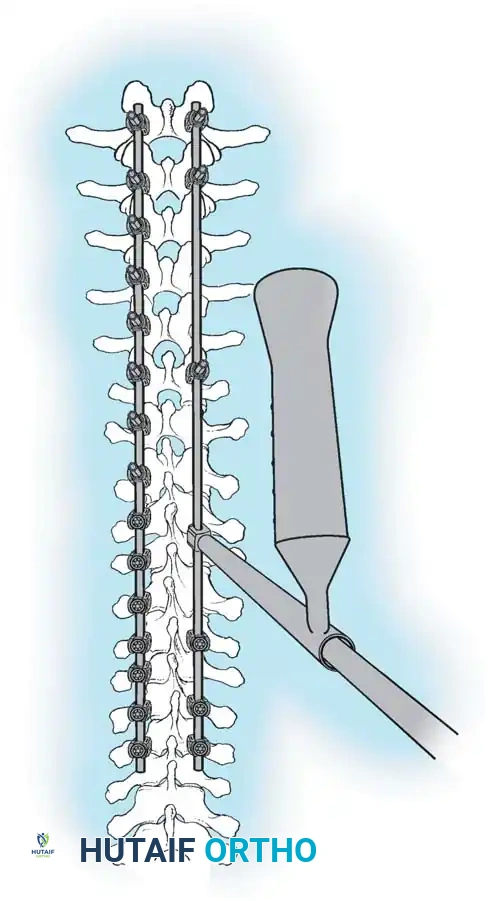

The Moe Technique (Lumbar Spine)

In the lumbar spine, the facet joints are oriented in a more sagittal plane, necessitating a modified approach.

Fig. 38-27: The Moe technique adapted for lumbar facet fusion, addressing the sagittal orientation of the joints.

- Utilize a small osteotome or a needle-nose rongeur to resect the adjoining joint surfaces.

- This creates a distinct rectangular defect within the sagittally oriented joint space.

- Pack this defect forcefully with cancellous bone graft.

- Proceed to decorticate the entire exposed posterior elements (laminae and transverse processes) using Cobb gouges, always directing force away from the spinal canal.